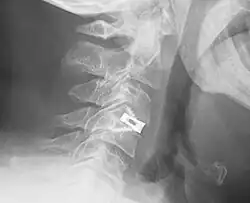

Interbody fusion cage

An interbody fusion cage (colloquially known as a "spine cage") is a prosthesis used in spinal fusion procedures to maintain foraminal height and decompression. They are cylindrical or square-shaped devices, and usually threaded. There are several varieties: the Harms cage, Ray cage, Pyramesh cage, InterFix cage, and lordotic LT cage, all of which are made from titanium; the Brantigan cage, made from carbon fibre; and the Cortical Bone Dowel, which is cut from allograft femur. The cages can be packed with autologous bone material in order to promote arthrodesis.[1] Such implants are inserted when the space between the spinal discs is distracted, such that the implant, when threaded, is compressed like a screw. Unthreaded implants, such as the Harms and Pyramesh cages have teeth along both surfaces that bite into the end plates.[1]